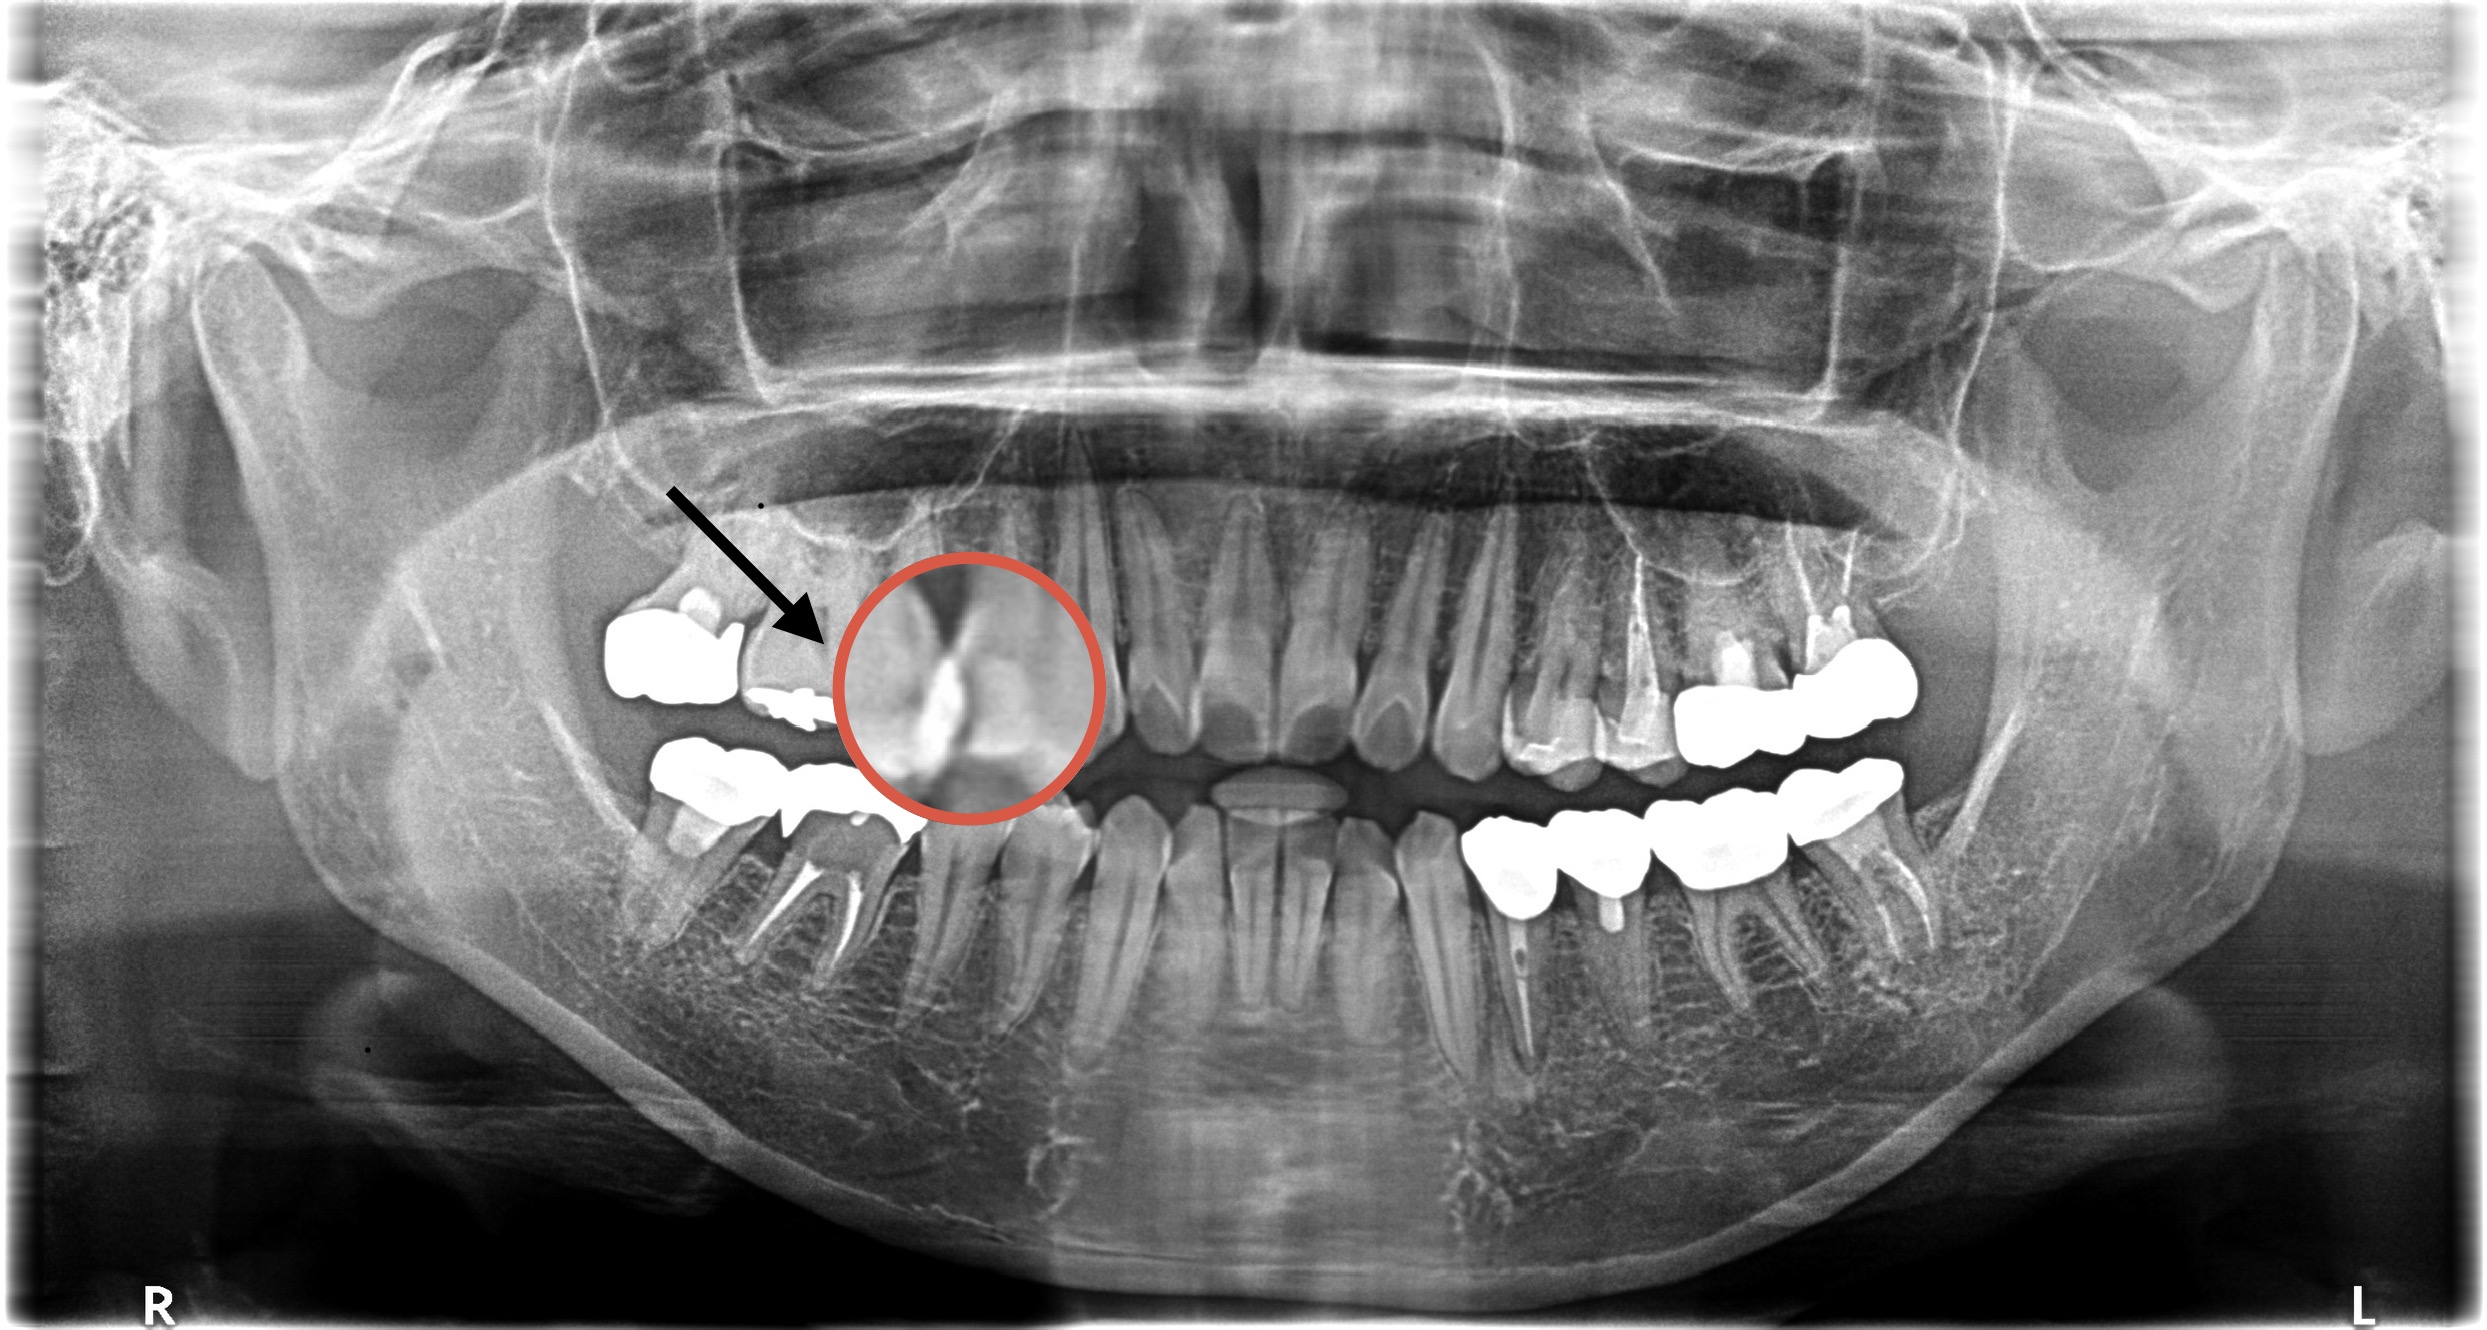

今回の症例では過去に虫歯治療を行い2次カリエスによりMTAセメントを使用し治療された方の紹介になります🦷

【右上第一小臼歯】